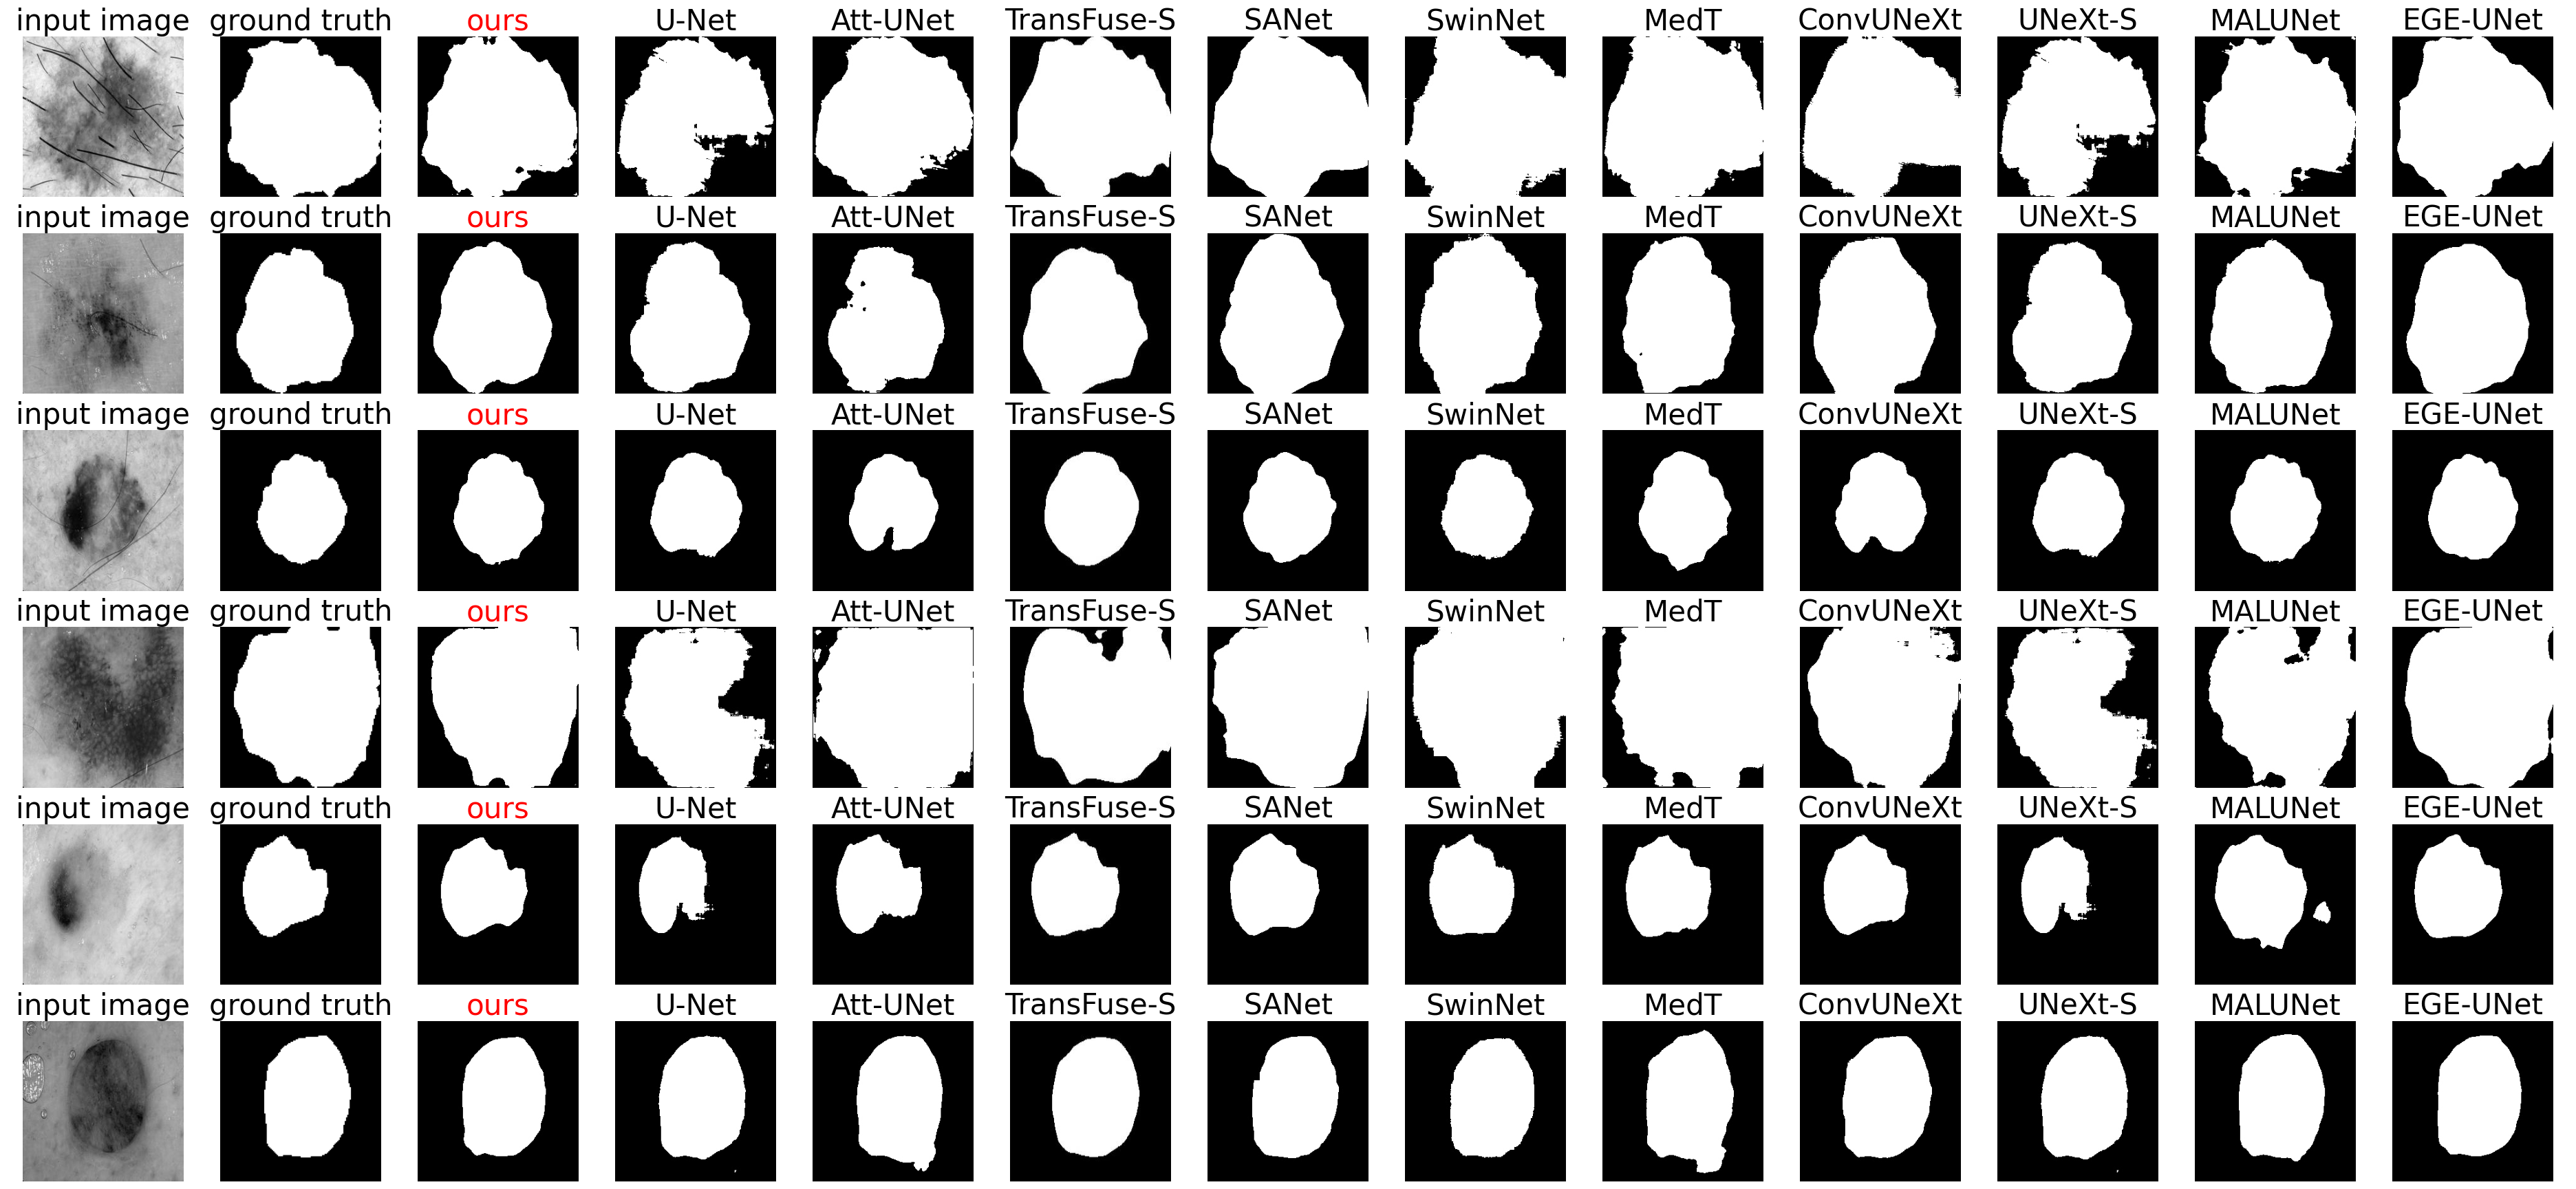

Table 1 comprehensively evaluates the performance of our UCM-Net, a novel skin lesion segmentation model, compared to well-established models, using the widely recognized ISIC2017 and ISIC2018 datasets. Introduced in 2023, UCM-Net is a robust and highly competitive solution in this domain. One of the key takeaways from the table is UCM-Net’s ability to outperform EGE-UNet, which had previously held the title of the state-of-the-art model for skin lesion segmentation. Our model achieves superior results across various prediction metrics, emphasizing its advancement in the field and its potential to redefine the standard for accurate skin lesion delineation. Moreover, UCM-Net’s performance is notably competitive even when compared to SwinNet, a model that relies on pre-trained models during training. Table 2 complements this assessment by comparing computational aspects and the number of parameters for various segmentation models. Remarkably, UCM-Net, operating with the same number of channels {8,16,24,32,48,64} and image size, as EGE-UNet, boasts fewer parameters and lower GFLOPs. Additionally, even when compared to TransFuse-S and SwinNet, which operate with smaller image sizes, UCM-Net demonstrates faster computational speed. In Figure 5, we present a visual exhibition of all the models’ segmentation outputs. This figure directly compares our segmentation results, those produced by other methods, and the ground truth, all displayed side by side using representative sample images. Notably, our segmentation results demonstrate a remarkable level of accuracy, closely resembling the ground truth annotations. Tables 1-2 and Figure 5 collectively underscore UCM-Net’s exceptional performance and efficiency in skin lesion segmentation, affirming its potential to make a substantial impact in advancing early skin cancer diagnosis and treatment.